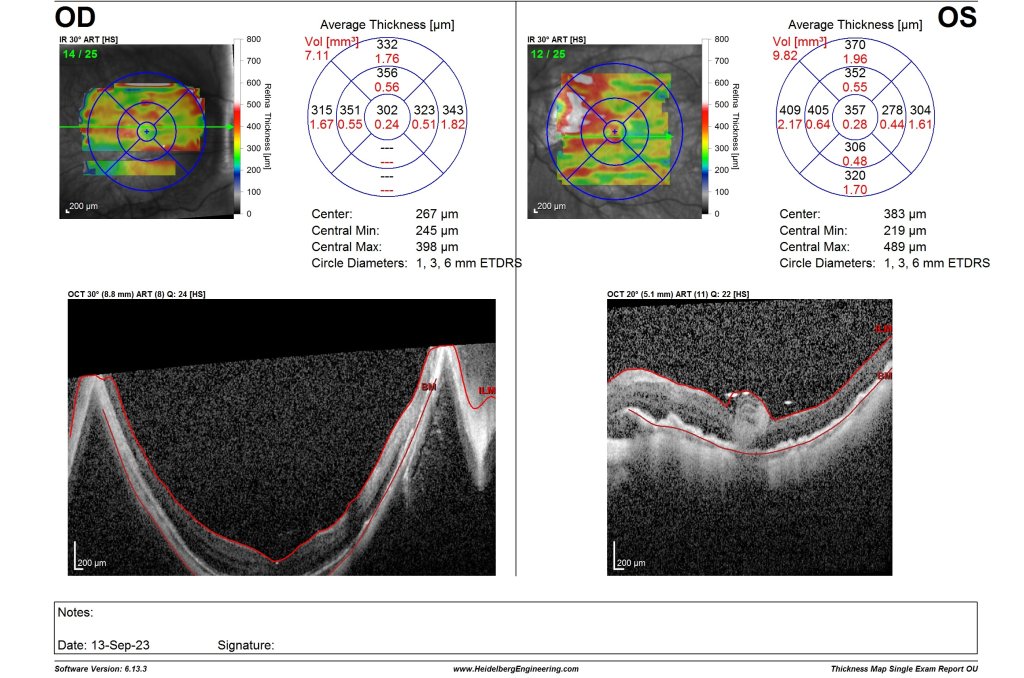

The first autologous retinal transplant (ART) was performed at Hospital Canselor Tuanku Muhriz on Thursday, 7 September 2023 by Professor Dr Mae-Lynn Catherine Bastion, vitreoretinal surgeon and senior consultant ophthalmologist from Department of Ophthalmology, Hospital Canselor Tuanku Muhriz and Faculty of Medicine, Universiti Kebangsaan Malaysia. She is also serves at UKM Specialist Centre. She was assisted by her fellow, Dr Lhacha Wangdi from University of Bhutan, Kingdom of Bhutan. The patient, a 58-year-old retired teacher with history of high myopia (short-sighted power of 18 dioptres) developed left blurred vision and seeing wavy lines (metamorphopsia) after her cataract surgery in January this year at another centre. Our examination found that she had a hole in her left eye macula, responsible for the drop in vision and symptoms. Surgery in the form of vitrectomy and peeling of the internal limiting membrane of the retina with gas bubble injection was performed uneventfully in June 2023. She reported improvement in her vision during her follow up. However, a small persistent hole was detected one month later which rapidly progressed to detachment of her retina (the delicate nerve tissue lining the back of the eye, responsible for vision). Hence she underwent a further left eye vitrectomy, this time with harvest of a small portion of her inferior retina, which was used to repair the defect at the macula (ART) , with the hope that the retina would remain attached after the surgery. She also received a heavy silicone oil bubble this time, allowing her to posture supine after surgery to maintain the graft position. Five days after the operation she is doing well. The picture below shows an optical coherence tomography (OCT) photograph of the graft positioned to cover the macula hole with attached retina surrounding it (Figure 1) and a photograph of the left eye shows the view of the graft (white) at the centre of the macula with the location of the graft site at the lower aspect of the photograph (Figure 2). In 6 weeks’ time, the heavy oil will be removed surgically and we hope she will obtain a good result.

Figure 1. Optical coherence tomography photograph of the ART graft covering the macula hole.